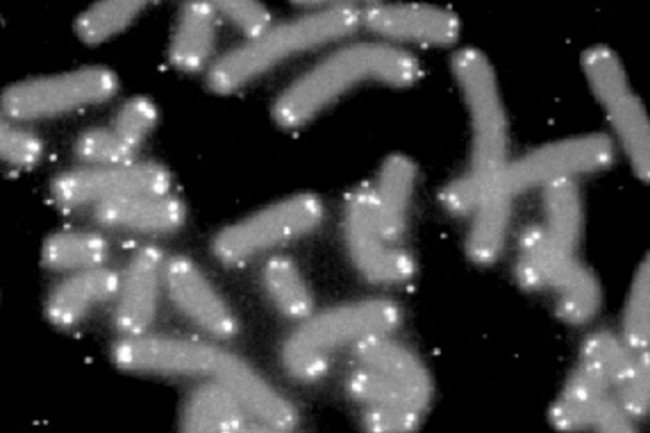

Giải pháp đầu tiên là thay đổi gen. Các nhà khoa học tập trung vào telomere, những trình tự lặp lại của DNA ở các đầu mút của nhiễm sắc thể. Mỗi lần tế bào tự sao chép, telomere sẽ ngắn dần đi và cuối cùng ngắn tới mức tế bào không thể tự tái tạo được nữa. Nói cách khác, con người già đi.

co the hoi sinh nguoi chet khong anh 3

Đoạn đầu của gen con người có thể giúp chúng ta trường sinh? Ảnh: Human Genome Program.

Nghiên cứu khoa học về những phương pháp trẻ hoá khác vẫn còn một quãng đường dài phía trước. Các nghiên cứu về telomere của nhà khoa học Elizabeth Blackburn đã được trao giải Nobel cho lĩnh vực Sinh lý học và Y học.

Đây đang là một hướng đi được đầu tư mạnh mẽ, nhưng chưa có nhiều kết quả nghiên cứu trong thực tế. Quan trọng hơn, nó cũng không đồng nghĩa với chìa khoá để loài người bất tử.